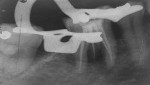

The intraoral periapical radiograph of the mandibular right first molar (tooth No. 30) showed radiolucency around the periapex with severe bone loss (Figure 3). Careful observation of this radiograph showed the presence of an additional distolingual root in relation to this tooth. The radiograph showed radiolucency in the furcation area with inter-radicular bone loss extending up to the apex of the distal and distolingual roots. Endodontically, the diagnosis was chronic apical abscess associated with necrotic pulp. Due to the associated advanced periodontal destruction, this lesion was classified as an endodontic-periodontal lesion. The formulated treatment plan comprised of drainage of the periodontal abscess with adjunctive antibiotics, phase I periodontal therapy (scaling and root surface debridement), endodontic therapy, and radiculoplasty, followed by regenerative periodontal therapy and replacement of the missing right mandibular second molar.

In the subsequent visit, the patient was asymptomatic. Clinically, there was no tenderness on percussion and no active pus drainage from the sinus tract, and the canal was dry. The periodontal status, however, remained unaltered. A master cone radiograph was taken (Figure 4) and obturation was completed using a single-cone technique and a mineral trioxide aggregate (MTA)-based root canal sealer. Restoration of the coronal access cavity was done using glass-ionomer cement followed by direct composite.